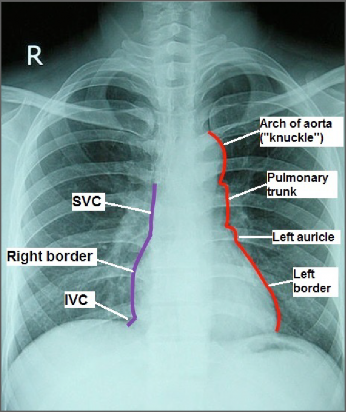

Borders (a.k.a. = margins) are not well defined on the gross heart, since it is conical in shape. However, they are important clinical entities used when examining the heart on X-rays or describing the radiological anatomy of the heart. On a chest X-ray, the silhouette cast by the heart next to the black lung fields (lungs are filled with air = black on X-rays) is defined by three borders:

• The right border is formed by the right atrium abutting the black field of the right lung.

• The left border is formed by the left ventricle and left auricle abutting the left lung.

• The inferior border is formed mainly by the right ventricle and a small bit of left ventricle. The shadow of the diaphragm obscures the inferior border.

Figure 13.13

Note also that on a chest X-ray the shadows of great vessels are seen merging with the right and left borders of the heart. From superior to inferior:

• On the right: SVC Right border of heart IVC

• On the left: Arch of aorta (seen as a “knuckle”—with its convexity to the left) Pulmonary trunk Left border of heart Apex of heart